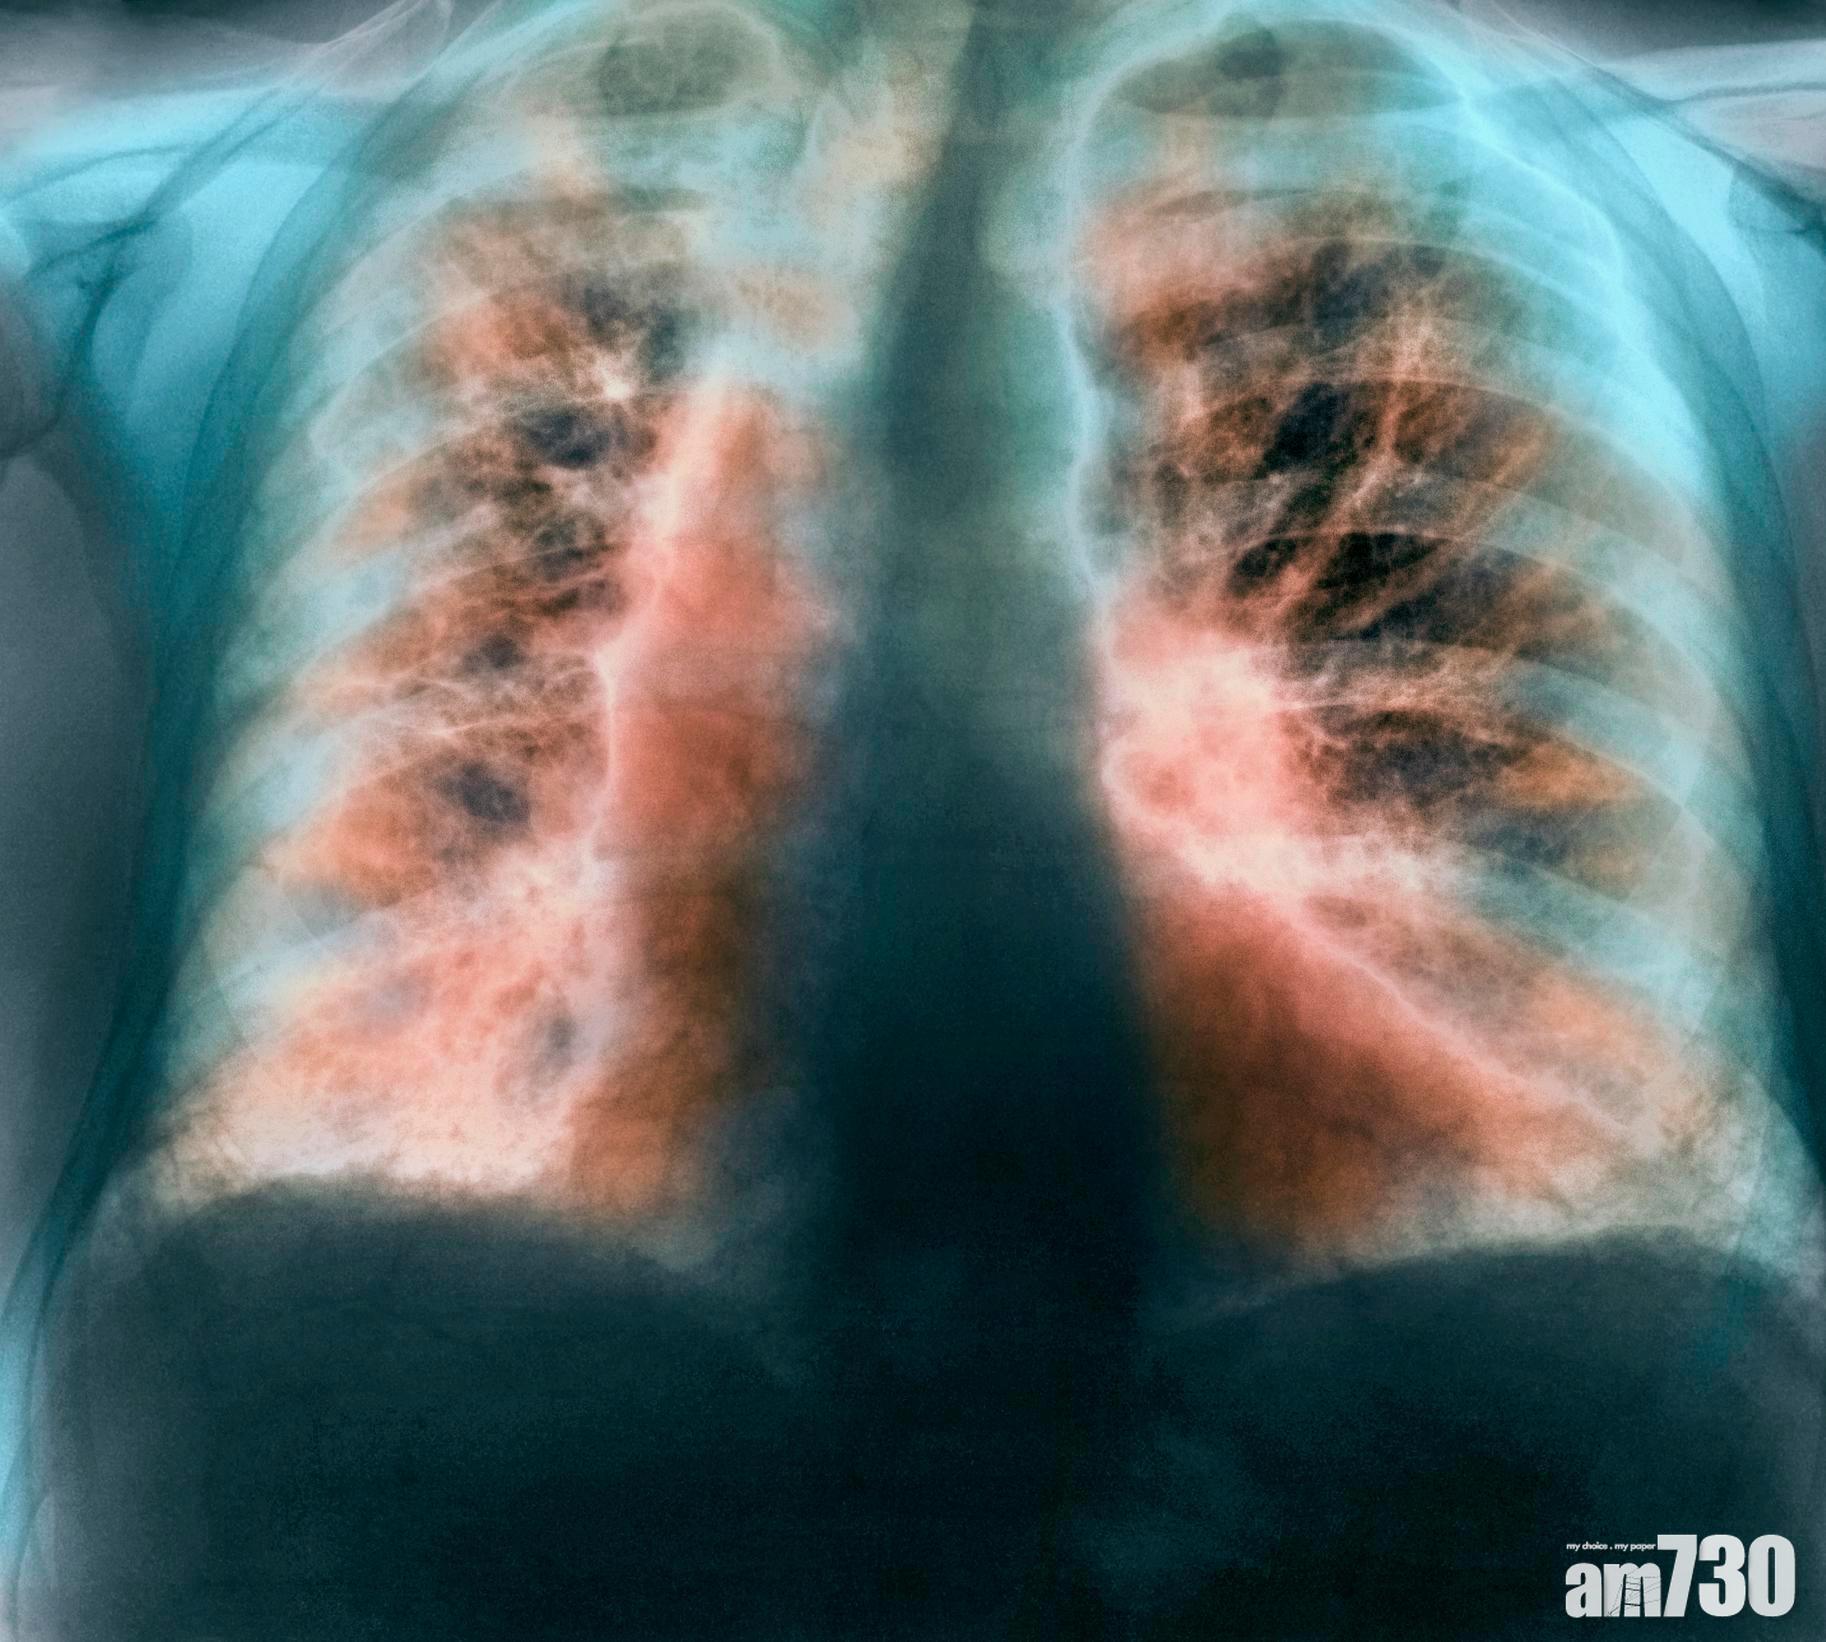

英國有研究表明,睡眠時間過長或不足,患上肺纖維化病風險高3倍。(互聯網圖片)

這種病因不明,但持續地肺間質因廣泛纖維化而造成的肺組織增厚,最終令肺部喪失正常氧氣交換功能。(互聯網圖片)